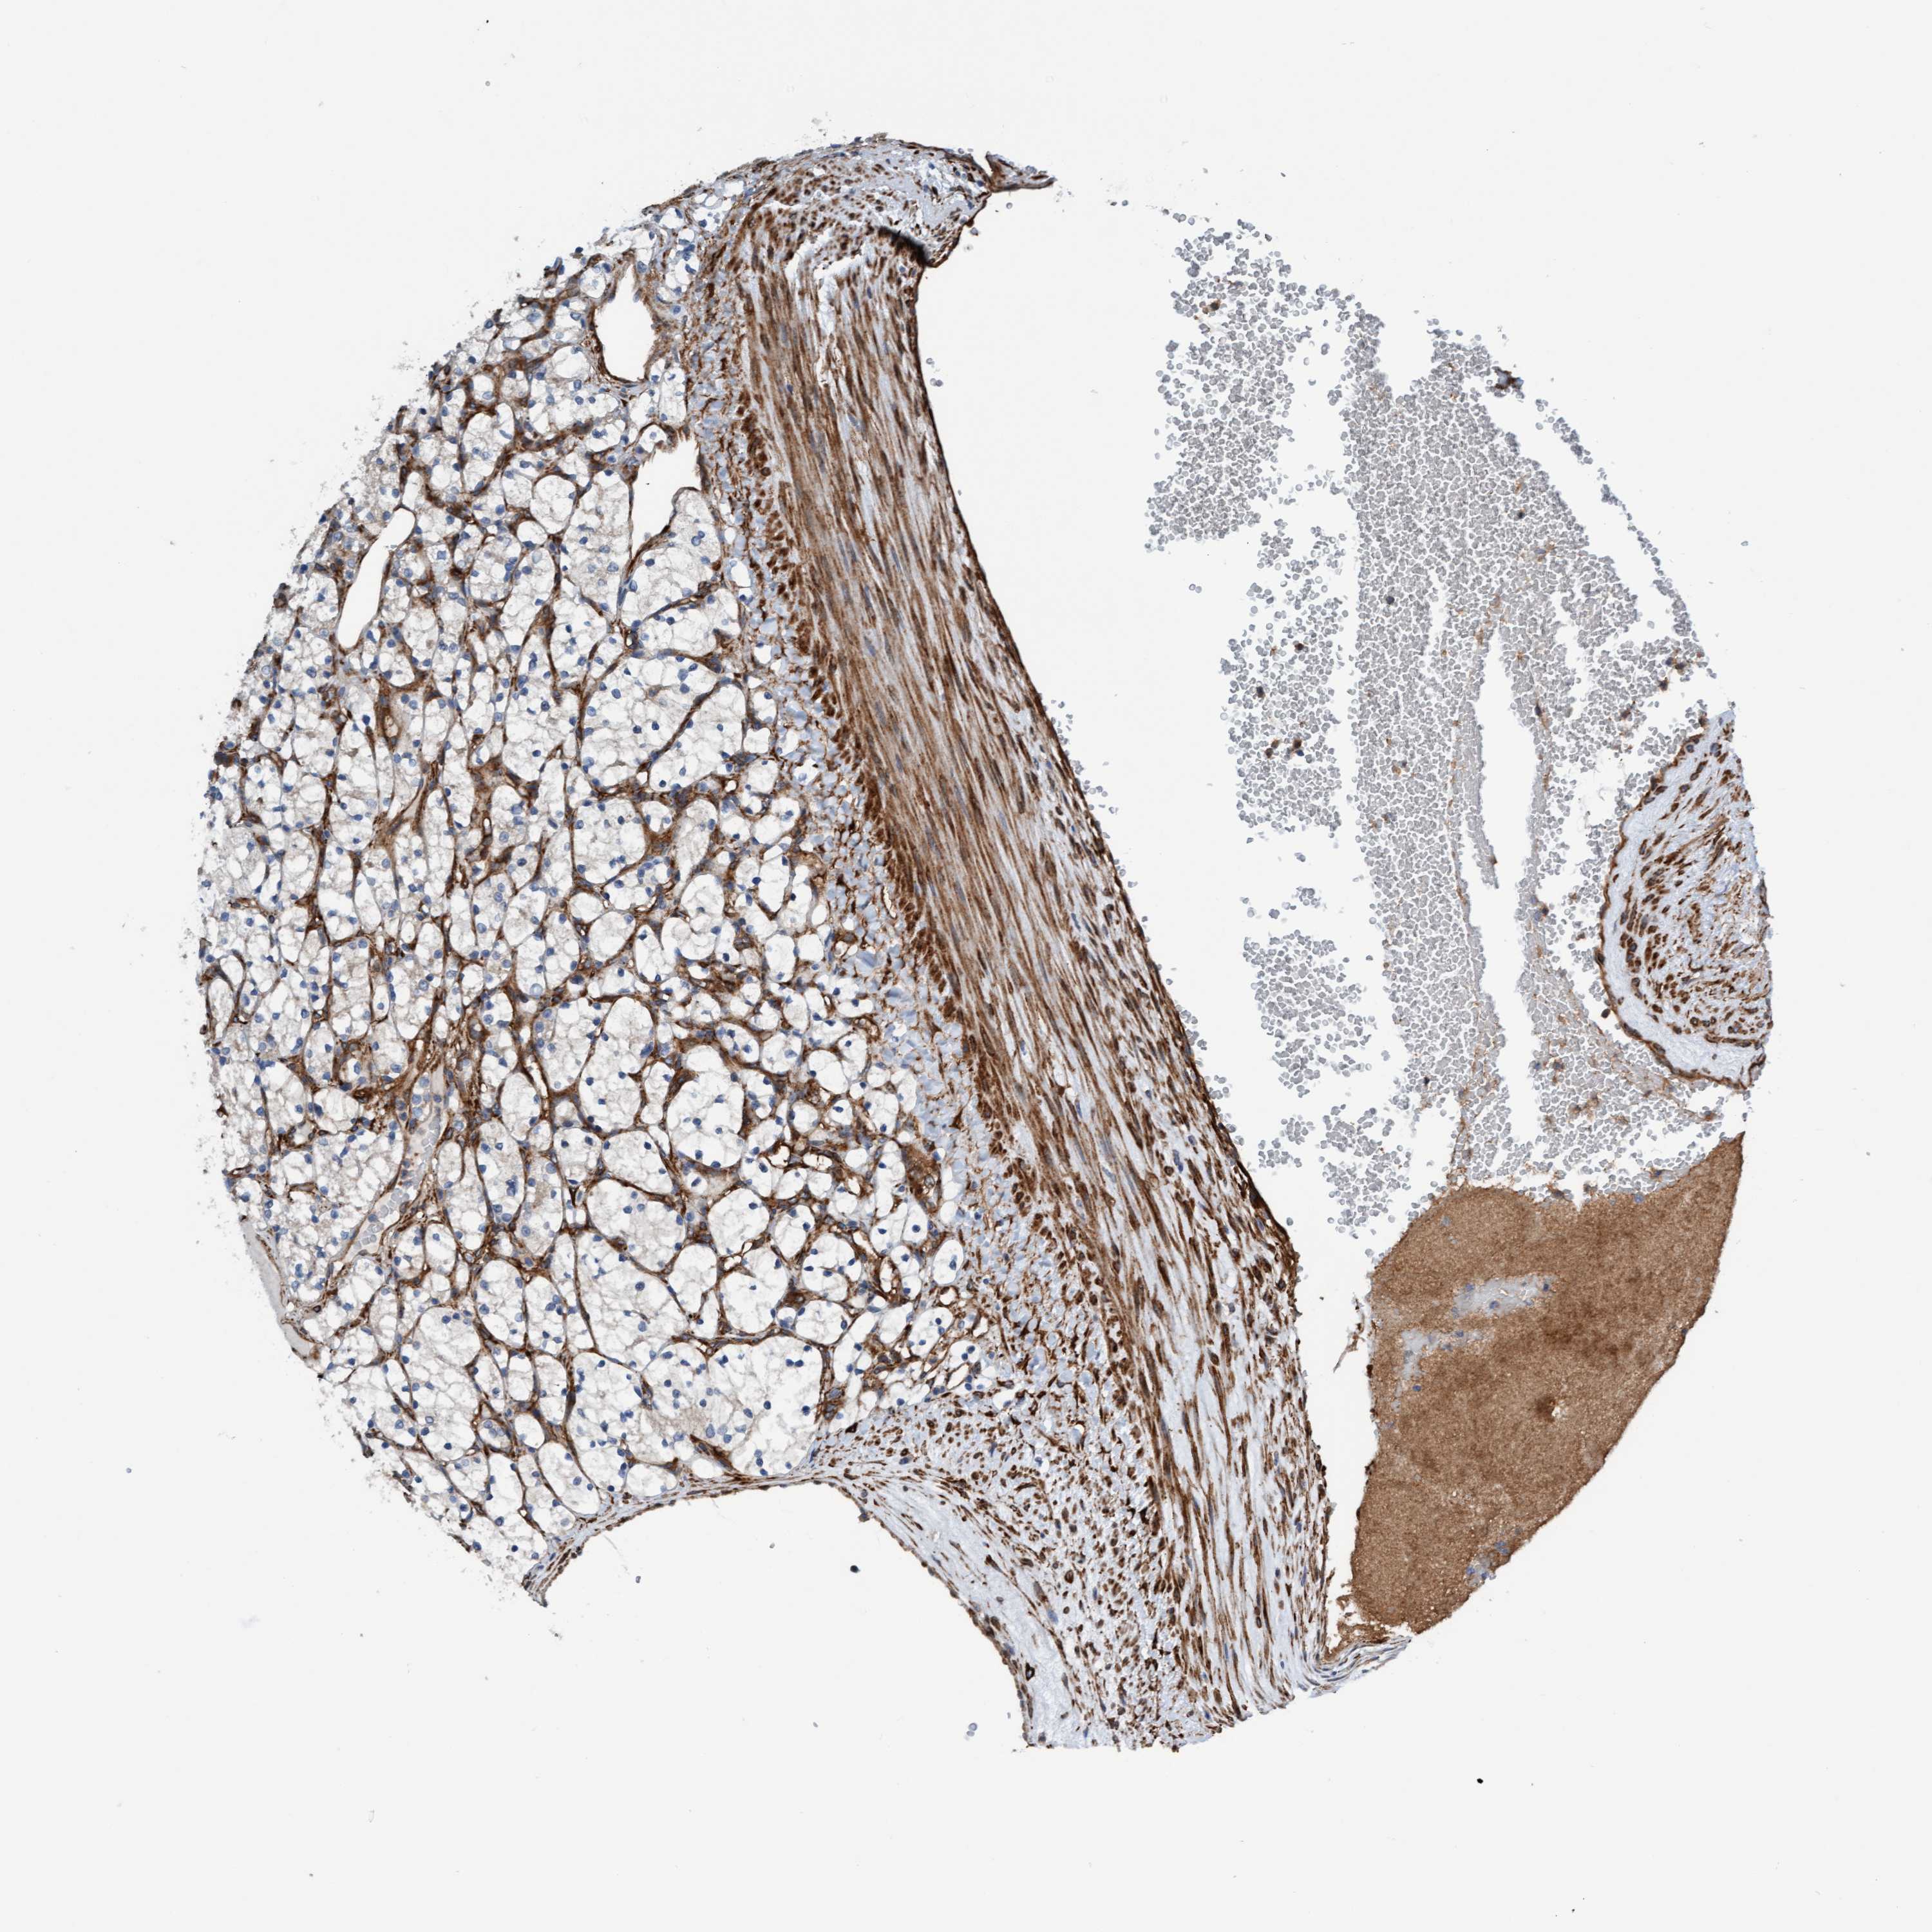

FMNL3 is validated prognostic, high expression is favorable in Kidney Renal Clear Cell Carcinoma (validation)

Best expression cut offi

Based on the FPKM value of each gene, patients were classified into two groups and association between prognosis (survival) and gene expression (FPKM) was examined. The best expression cut-off refers the FPKM value that yields maximal difference with regard to survival between the two groups at the lowest log-rank P-value. Best expression cut-off was selected based on survival analysis .

When clicking on this number, the vertical dashed line indicating cut-off, the interactive survival plot, and the Kaplan-Meier curve will be adjusted to show results based on the best expression cut-off.

: 27.36

Average pTPM 23.2

Number of samples 100